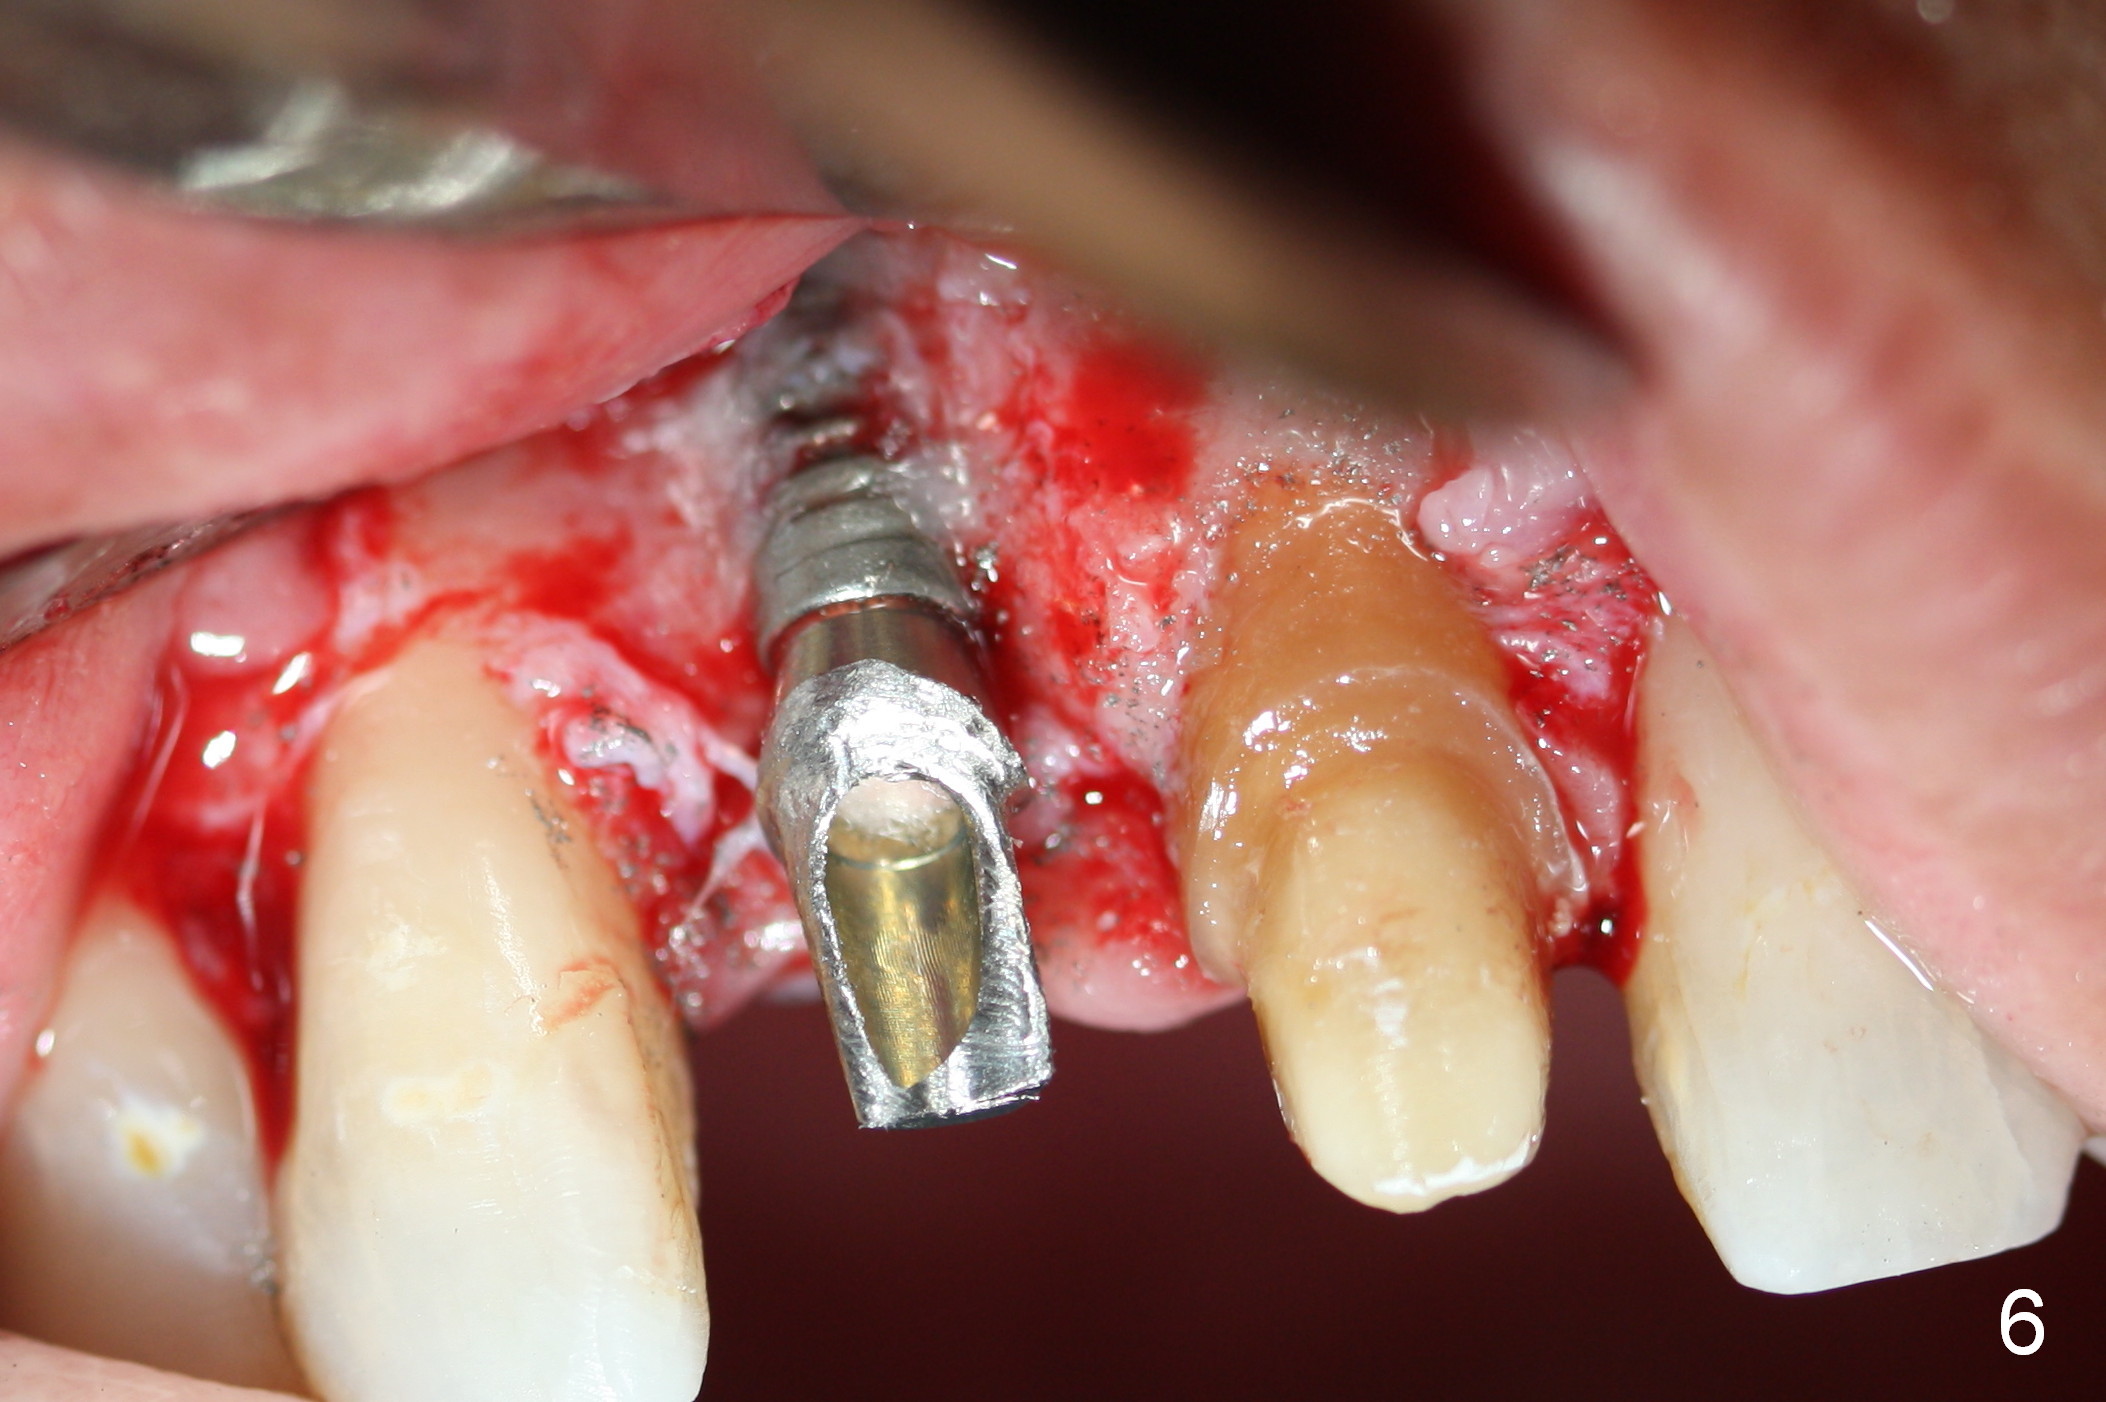

The patient returns for Zirconium abutment retrieval 1 month post its fracture.  When the provisional is removed, the gingival pontic morphology remains (Fig.2).  There is no problem to remove the abutment screw (Fig.1 with its driver), whereas it is difficult to remove the remaining abutment (Fig.2 *) due to limited access.  When the access improves by incision (Fig.3), buccal implant thread exposure is confirmed and the fractured abutment (*) is to be removed easily.  A 15° angled abutment (A) corrects the angulation, but not the position (Fig.4,5, compare to Fig.1 with a driver in place).  After being trimmed, the labial contour of the abutment is equivalent to that of #9 (Fig.6,7), but the margin is higher.  Using an abutment with taller gingival height (from 2 mm to 3 mm) may alleviate the margin issue.